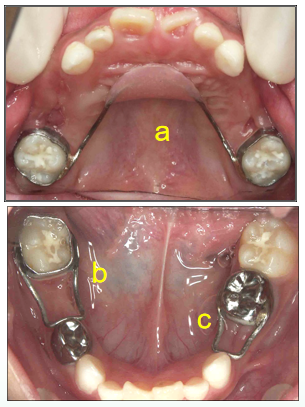

图为7岁患者佩戴了3种固定式间隙保持器。

a为腭弓,是用于多颗乳磨牙早失的上颌腭弓间隙保持器。

b为带环丝圈式、c为全冠丝圈式,b和c都是早失牙齿数目较少时佩戴的间隙保持器。